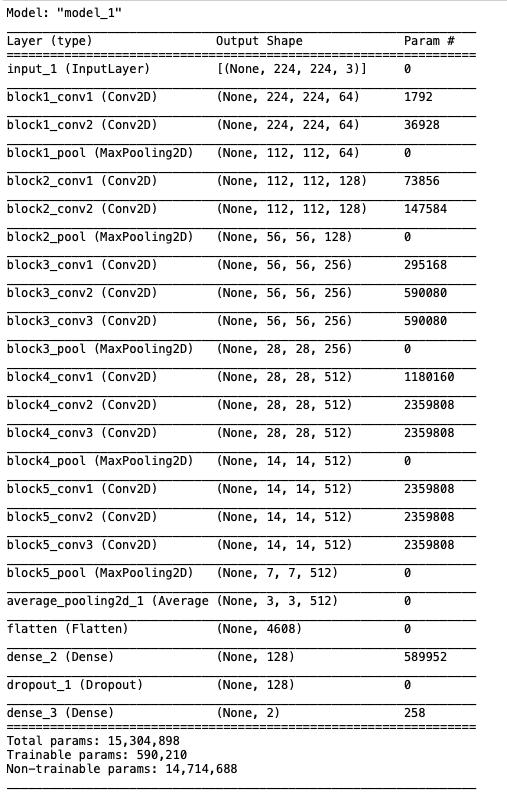

在我们的例子中,最后两层(FC1和FC2)是在本地训练的,参数总数超过1500万,其中大约有590000个参数是在本地训练的(而其余的是“frozen(冻结的)”)。

首先,让我们检索模型并显示最终的体系结构,以检查一切是否正常:

new_model = load_model('../model/covid_normal_model.h5')# 展示模型架构new_model.summary()

这个模型看起来不错,是VGG16的16层结构。请注意,可训练参数为590210,这是最后两层的总和,它们被添加到参数为14.7M的预训练模型中。